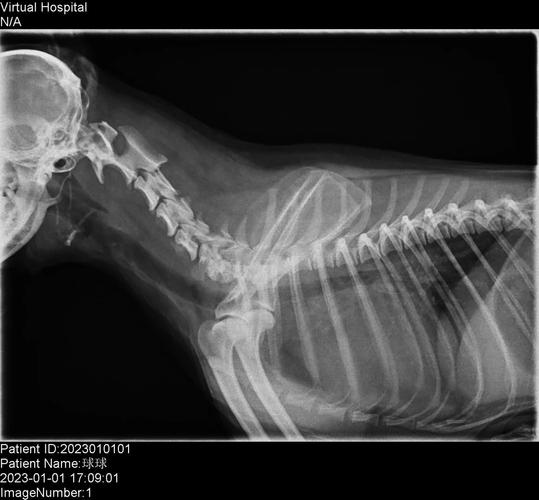

狗狗也会有颈椎病

〖壹〗、狗狗出现颈椎病的原因 常见的可能患病的情况有两种:狗狗头部突然受到外力的撞击从而导致颈椎出现了错位 长期低头、肌肉紧张造成劳损过度、颈椎变形等,压迫神经。其实在我们家中最容易导致狗狗颈椎病的是狗狗的进食,这是大家都经常会忽略的。

〖叁〗、颈椎疾病:狗狗可能患有颈椎病,这是一种常见疾病,会导致颈部疼痛、僵硬和活动受限。颈椎病的发生可能与遗传因素、饮食不当、营养不良、长期不正确的姿势、运动过度以及年龄增长导致的骨骼磨损等因素有关。颈椎病的症状还包括头晕、呕吐、四肢麻木等,严重时可能压迫神经,引发更复杂的神经症状。

小狗突然全身瘫痪很有可能是患有颈椎病,而且病情已经非常严重。颈椎病严重的症状有全身瘫痪,大小便失禁等。脊柱神经发炎也会导致狗狗全身瘫痪,与颈椎病一样,都是神经出现问题导致的。当小狗严重缺钙的时候,也可能会出现全身瘫痪的情况。平常的表现还有身体抽搐、四肢无力、目光呆滞等。